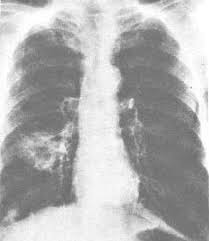

Para Dokter biasanya mendiagnosa Penderita kanker paru dengan jalan foto X-Ray, CT Scan Toraks, Biopsi Jarum Halus, Bronkoskopi, dan USG Abdomen.